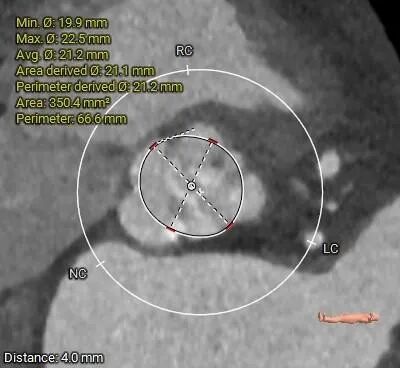

术前CT评估

• 三叶式主动脉瓣,瓣叶增厚,R-L交界增厚粘连,轻度钙化,钙化主要沿无冠窦瓣缘分布;LVOT近似直筒型;

• 瓦氏窦内径尚可,STJ小于30mm,升主动脉无扩张,瓣上40mm处测得约33.7mm;

主动脉根部评估

• 三叶式主动脉瓣,瓣叶增厚,R-L交界疑似增厚粘连,轻度钙化,钙化主要沿无冠窦瓣缘分布,LVOT近似直筒型,预估假体瓣膜植入锚定难度适中,结合瓣环及瓣上分析尺寸,选择TaurusElite AV23瓣膜,可以保证充分锚定力且径向支撑性好;